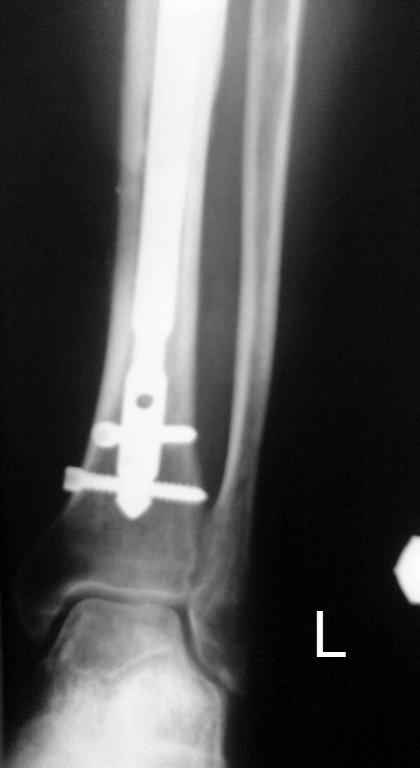

Кратко: мужчина за 60 лет получил травму 28 лет назад (переехало автобусом). Оперировался десятки раз, в итоге с очередным патологическим переломом, хронической язвой и гипсовой лонгетой попал ко мне... Объективно - остеомиелит, инфицированный ложный сустав (или как его назвать), флегмона по наружной поверхности

голени, укорочение около 5 см.

На операции резекция 8 см, внешний остеосинтез,одновременное сближение примерно на 4 см, а затем постепенное сближение до полного контакта в течение 3 недель. Рана с патологически измененными краями, имевшая на операции размеры примерно 4-5 на 10-12 см закрылась самостоятельно в течение примерно 2-х мес. Ну не самостоятельно, конечно, а с нашей помощью, но без пластики.

Сейчас в аппарате вытянул около 6 см в верхней трети.